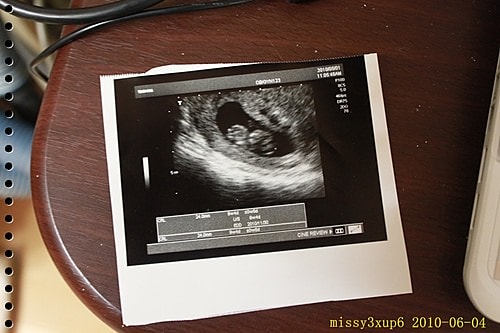

總而言之,我拿到了第二本媽媽手冊,也拿到了第一張二寶的照片了^^。

看著這張超音波照片,因為二寶躲的太裡面,桓爸這次還是沒親自看到二寶,只看到了照片,他還怪說是桓兒太吵,嚇到二寶了XD。

二寶看起來很活潑,一直跳,手手腳腳也一直揮。

在又看到超音波的瞬間,我好感動,這是我得孩子,他依舊很健康的在我肚子裡面活動。

現在又看了下照片,他的肚子好大唷>/////<。

拍得不好,我只是想紀錄一下大概的樣子><,有點光影我也懶得重拍了。